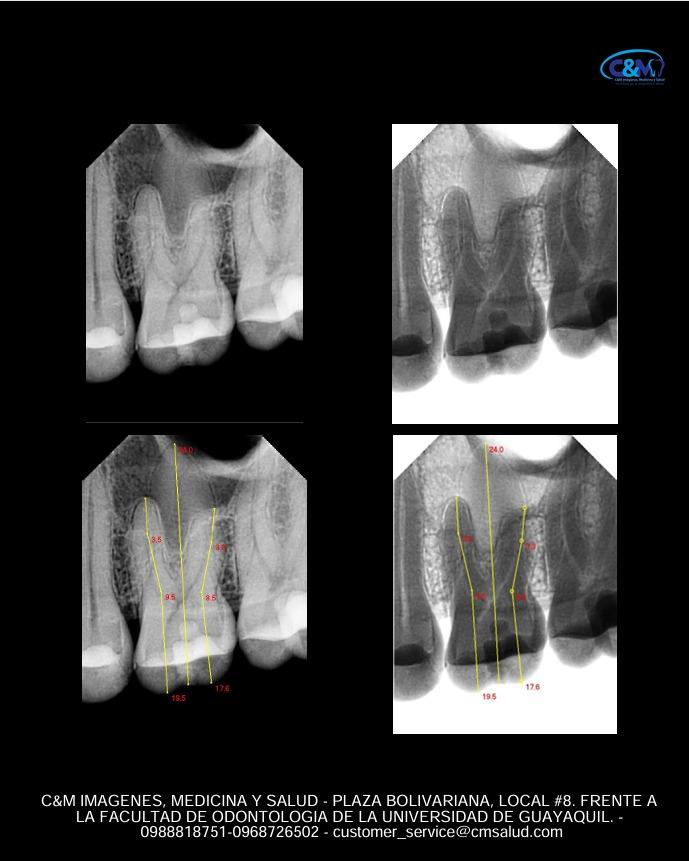

PERIAPICAL PLUS

PERIAPICAL DIGITAL